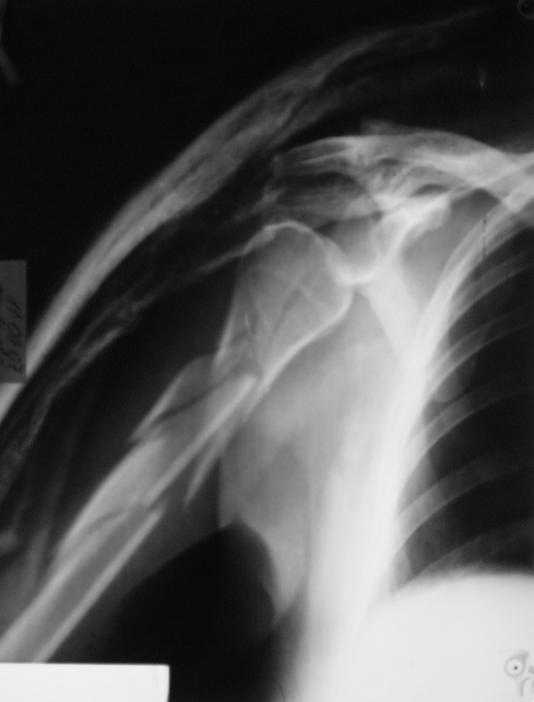

Немножко переделал повязку с отведением, подправил, вот что получилось.

Перелом внутрисуставной, Вы уверены на счет Сармиенто? На первичном снимке не видно было перелома головки.

В наших условиях выбрали бы закрытое штифтование проксимальным гвоздем для плеча T2 Stryker. Голоку предварительно бы фиксировали спицами вне траектории гвоздя, чтобы не разобщить отломки.